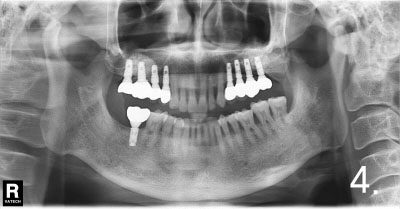

Case #2

Before the surgery. There is not enough bone at back site to place implants

Implant placement and sinus bone graft were performed simultaneously on right side. Only sinus bone graft was performed on left side due to the lack of the residual bone to place implant simultaneously

Implant placement was performed a few months after sinus bone graft

All implant crowns were fabricated and delivered. All teeth functions were restored.